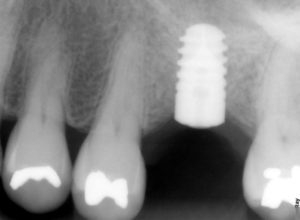

NeoBiotech (Корея) одна из лучших имплантационных систем с конусным соединением в эконом сегменте. Используется для съемного и несъемного протезирования. Имеет широкую линейку размеров, что позволяет применять Корейские имплантаты Необиотек практически при любой патологии и рекомендовать их пациентам с различными индивидуальными показаниями.

NeoBiotech – это современная система имплантации, которая заняла прочные позиции на современном украинском рынке. Используются как для постоянных, так и для съёмных протезов. Импланты прекрасно подходят как для мгновенной установки, так и для двухэтапной. Производителем был разработан уникальный дизайн BioSeal. Благодаря этому дизайну снижается степень атрофии и рассасывания кости. При производстве используются исключительно качественные материалы. Покрытие S.L.Active гарантирует максимальную приживаемость протеза к кости значительно лучше всех своих конкурентов.

Импланты НеоБиотек изготавливаются по специальной технологии. Они имею конусовидную форму, которая обеспечивает лёгкость и высокую скорость установки. Также немаловажным фактом является то, что конструкция изготовлена из материалов очень высокого качества, которые не нанесут никакого ущерба организму пациента.